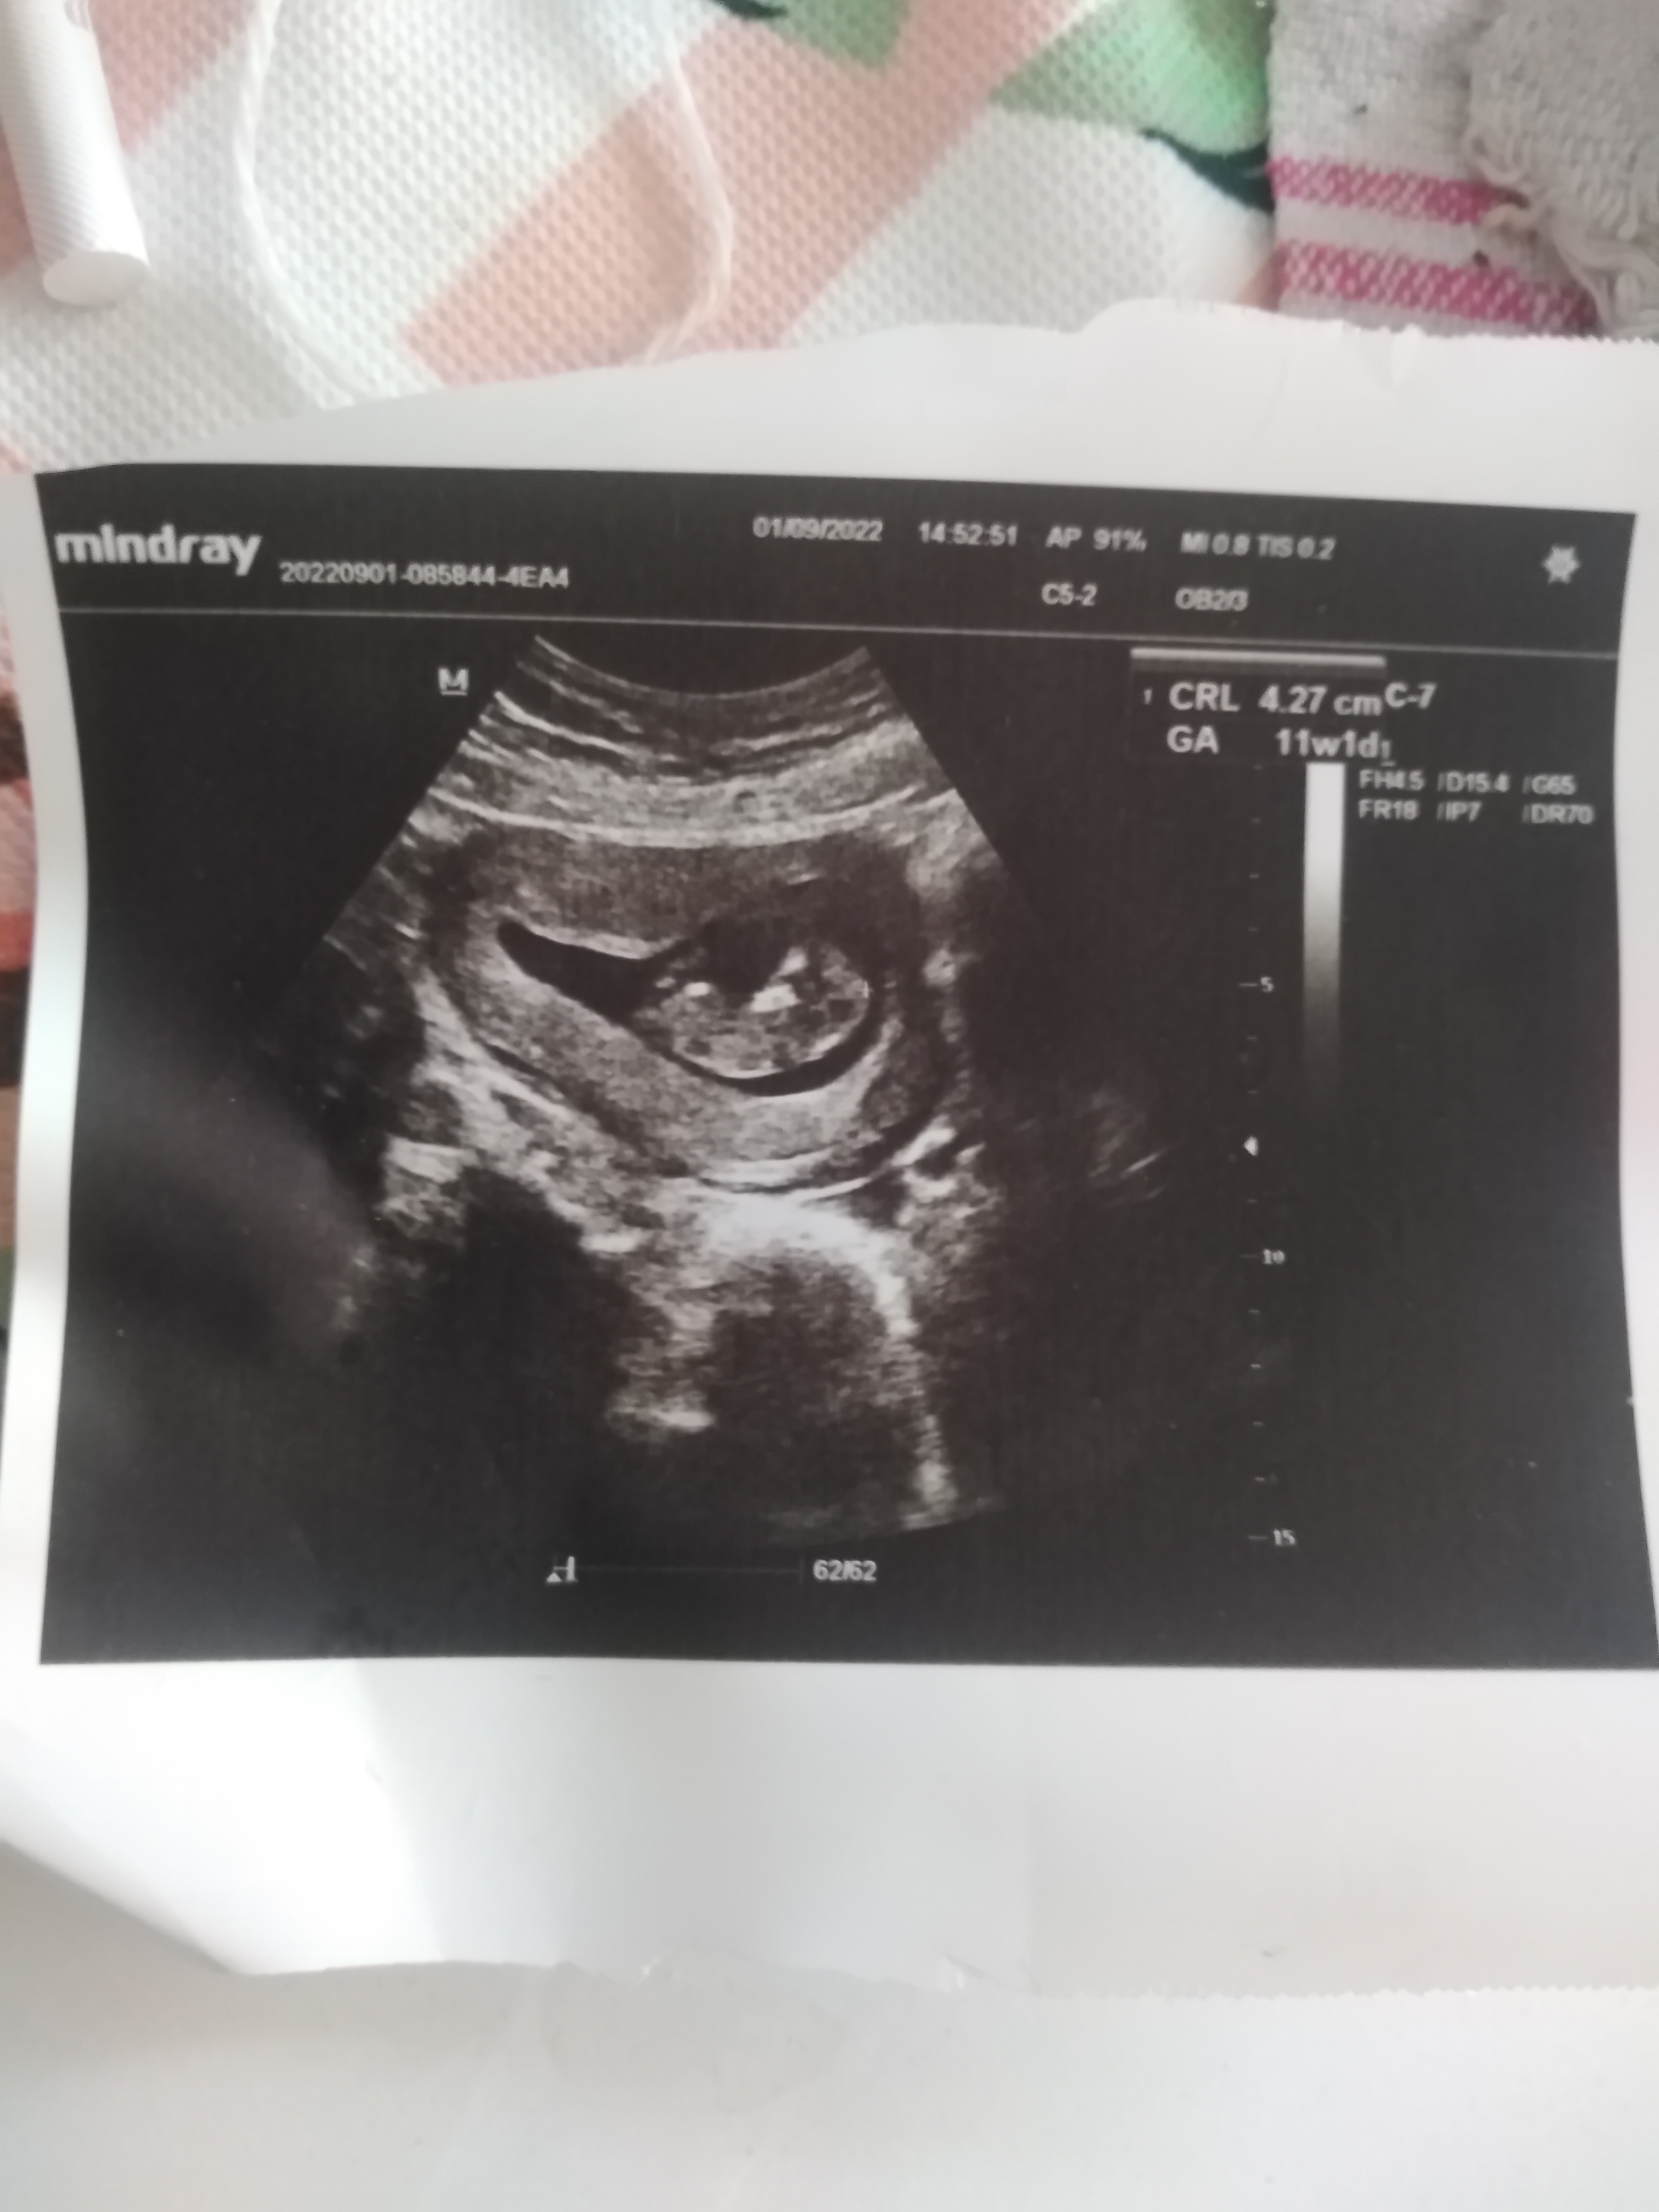

D Dilosssss Yeni Üye Üye 2 Eylül 2022 #779 Uzman SühaN' Alıntı: Merhaba , Resim yükleyebilmeniz için üye olmanız gerekiyor. Ayrıca yukarda ki görsel kadar net ise usg görüntünüz yorumlayabilirim. Genişletmek için tıkla ... Benimkinide yorumlar mısınız lütfen Ekli dosyalar IMG_20220901_164910.jpg 1,8 MB · Görüntüleme: 187

Uzman SühaN' Alıntı: Merhaba , Resim yükleyebilmeniz için üye olmanız gerekiyor. Ayrıca yukarda ki görsel kadar net ise usg görüntünüz yorumlayabilirim. Genişletmek için tıkla ... Benimkinide yorumlar mısınız lütfen